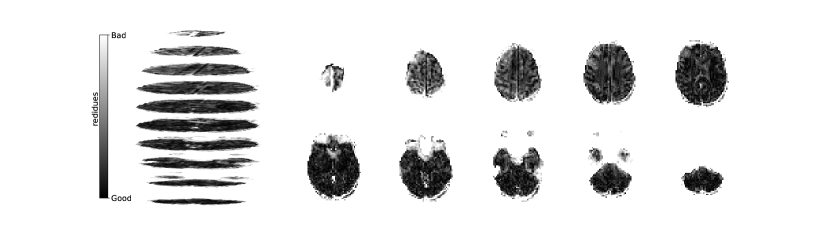

Figure 2 illustrates the distribution of residues (observed vs. estimated differences) on the fMRI volumes for the NODDI dataset. Clearly, by visual inspection, (iv) model has the darker and biggest area of shaded regions, which implies a better coverage across the brain regions and better synthesis quality. Models with topographical attention, (ii) and (iv), corresponding to Figures 2(b) and 2(d), respectively, significantly improve the synthesis, as shown by the darker and bigger areas against (i) and (iii) depicted in Figures 2(a) and 2(c), respectively. Particularly, we notice that models (i) and (iii) report difficulty in the retrieval of haemodynamical activity located in occipital and parietal lobes.

To better address which regions our baselines had more difficulty retrieving, the normalized residues were computed and are illustrated in Figure 3. Baselines – corresponding to models (i) and (ii), shown in Figures 3(a) and 3(b) respectively, which correspondingly implement a linear projection in the latent space and topographical attention –, have difficulty retrieving the prefrontal, occipital and parietal lobes, as the shade tends to a lighter grey in that region. Model (iv), shown in Figure 3(d), does not show a noticeable region with a lighter tone of grey, which implies no evident difficulty in retrieving haemodynamical activity across the different brain regions.